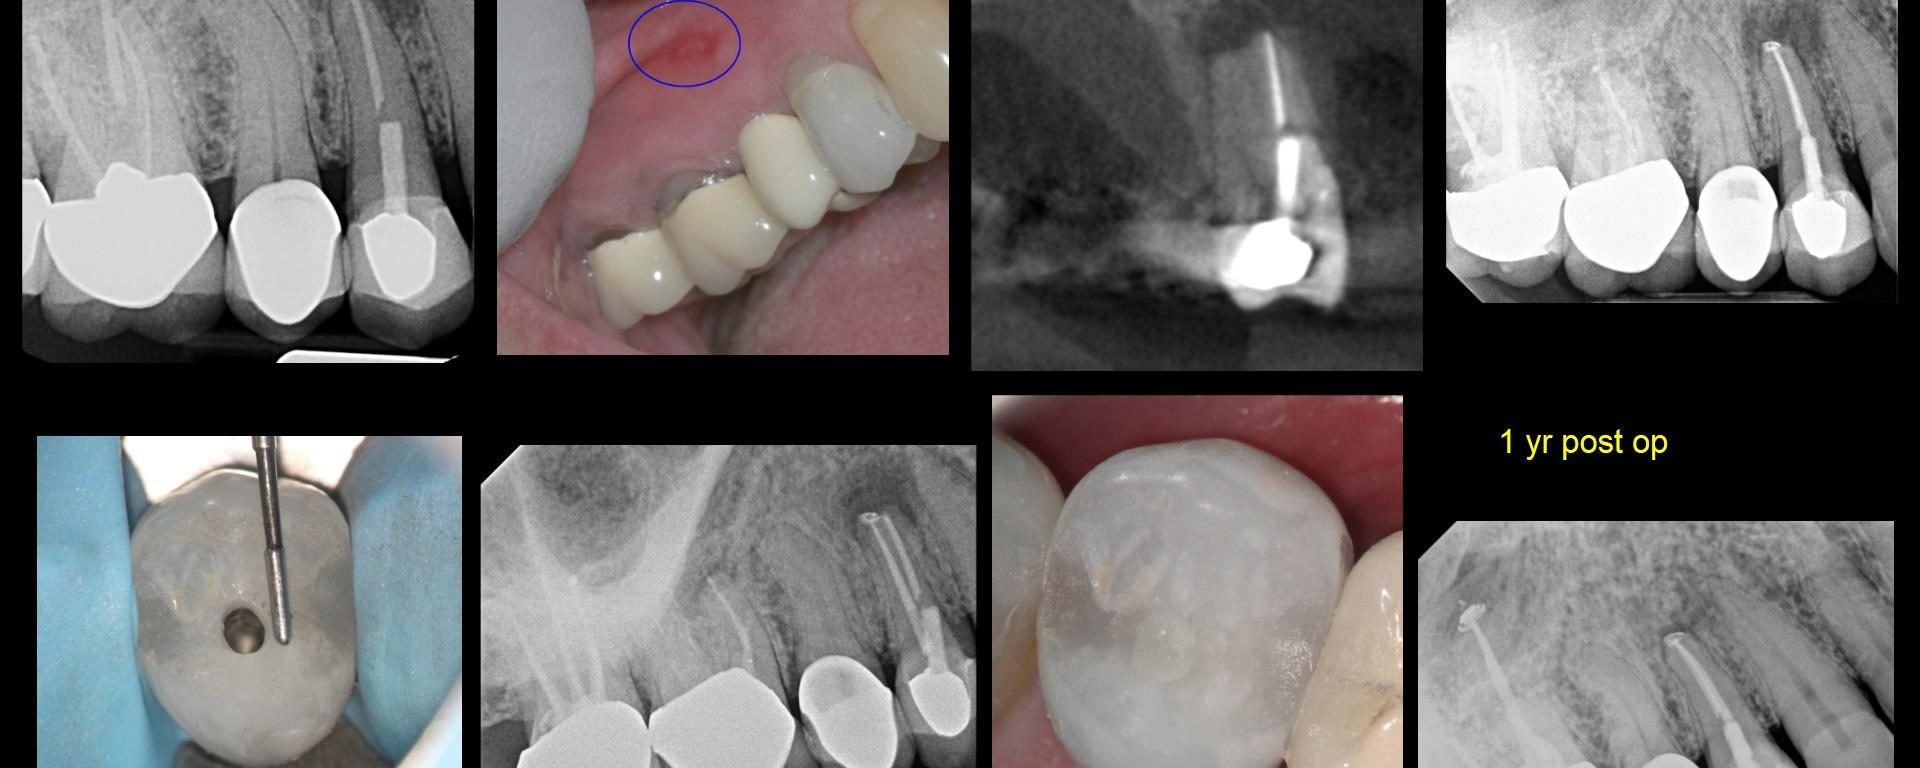

Pt presented with persistent sinus tract on B

July 27, 2018 27 comments

Pt presented with persistent sinus tract on B. RCT’s done by another endodontist in town. They were suggesting to start endo in #26 followed by apico if that did not work. That’s when she decided to go for another opinion. I retreated #23 and 24, CaOH for at least 6 weeks, with no luck. Sinus […]